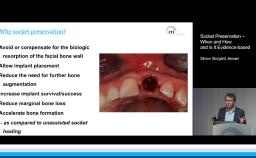

This lecture summarizes the morphological changes that follow tooth extraction and gives hints on how to minimize atrophy of the bony walls using atraumatic techniques and selected filling materials. Dr. Chen provides research evidence for various ridge preservation techniques and shares the characteristics of an ideal filling material. He also presents the clinical indications for each technique, including post-extraction ridge maintenance, immediate (Type 1) implant placement, and ridge reconstruction.

- describe the morphological changes of the alveolar walls after tooth extraction

- describe the effect of different filling materials on the bone resorption

- choose the optimal technique to minimize the resorption process